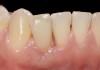

Problem: The implant is placed too facial with significant recession on the midfacial aspect of the abutment and/or crown; the implant is healthy and the patient has a high smile line with an intermediate to thick periodontal phenotype (Figure 1 and Figure 2).17-19

Fig 1. Midfacial recession can affect the esthetics of a smile and lead to an unsatisfactory outcome.

Fig 2. The cause for midfacial recession is excessive labial implant placement. Secondary to poor placement is overcontouring of the implant abutment.